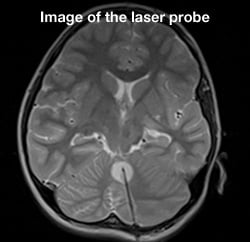

Laser ablation brain surgery

On May 29, 2013, Cook Children's became the first pediatric hospital in North Texas to perform iMRI-guided laser ablation brain surgery. For the patient, it was a triple win. He was the first to undergo this surgery, and the first at Cook Children's to have this surgery for epilepsy. But the biggest win of all was that just 24 hours after the surgery, the patient was seizure-free and discharged from the hospital. Being the first to perform this surgery wasn't the only benchmark we set that day. We raised the bar on more effective treatment for kids with epilepsy and brain tumors.

Currently, only 10 pediatric facilities in the U.S. offer this amazing surgery. Also known as stereotactic laser ablation, this iMRI-guided, minimally invasive procedure allows abnormal tissue to be thermally destroyed in real time. The surgery takes place in our iMRI suite, which reduces patient's surgery and anesthesia time and allows for targeted abnormal tissue removal, with little to no risk to surrounding brain tissue. Most patients go home within 24 hours and with only one stitch.

Laser ablation uses targeted light energy to destroy tumors and damaged tissue. Using guided iMRI technology, the doctors can see precisely where the tumor or lesion is in the brain and the laser energy can then be delivered right to the targeted area.

- A 3.2mm hole is drilled for cranial access.

- The patient is placed into the iMRI.

- The surgeon guides the laser into position using imaging and then thermally destroys the abnormal tissue.

- The laser applicator is removed and a stitch is placed to close the incision.